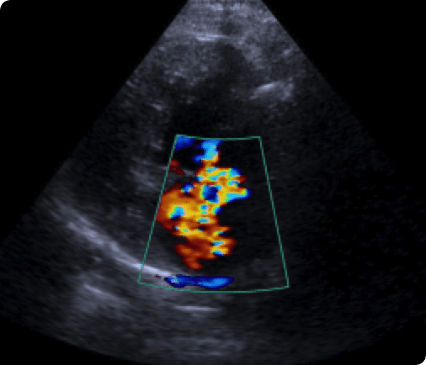

최고사양의 Siemens Sequoia 초음파 장비를 갖추고 있습니다.

일산시티동물의료센터는 최신 고해상도 초음파 장비를 통해 세밀하게 심장을 정밀하게 분석하여 심장질환을 진단합니다.